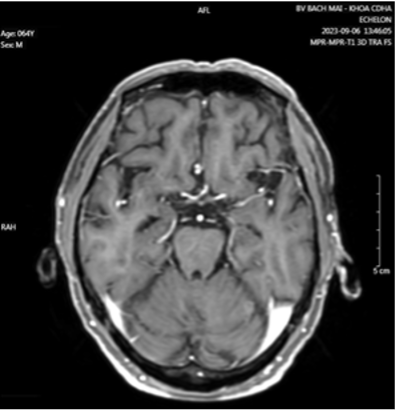

Hình 5: Hình ảnh teo não theo tuổi.

Cộng hưởng từ sọ não có tiêm thuốc đối quang từ: